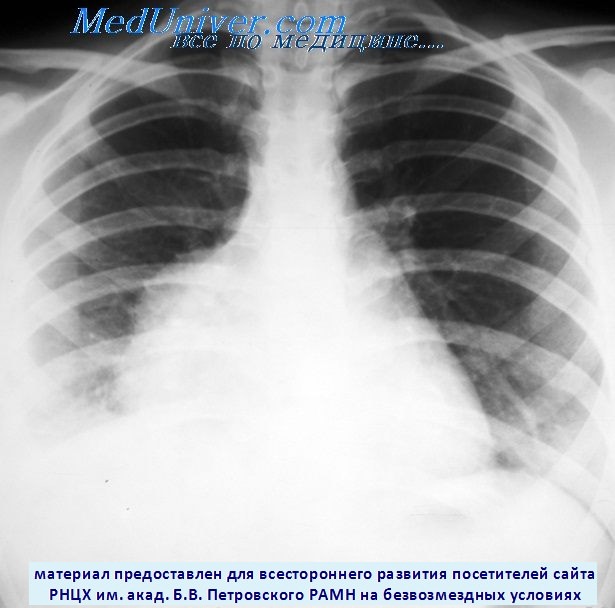

Рентгеновские снимки тератомы средостения: Диагностика и лечение

Раздел: Фотоэссе